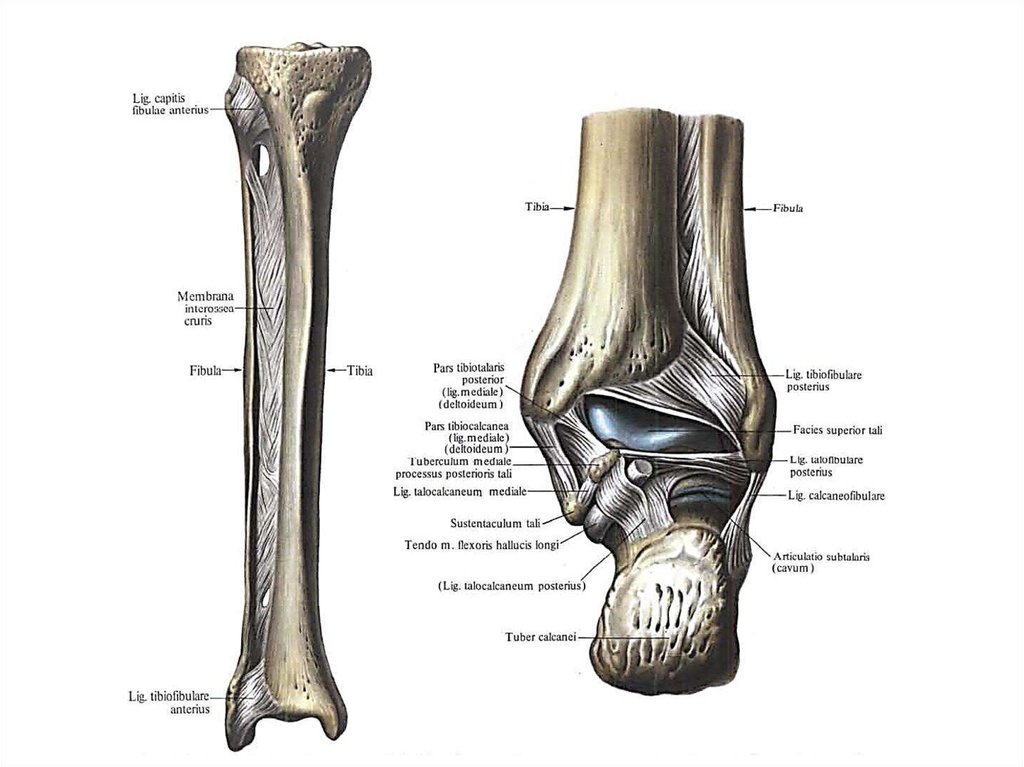

Анатомия фибулы: Подробные фотографии и схемы